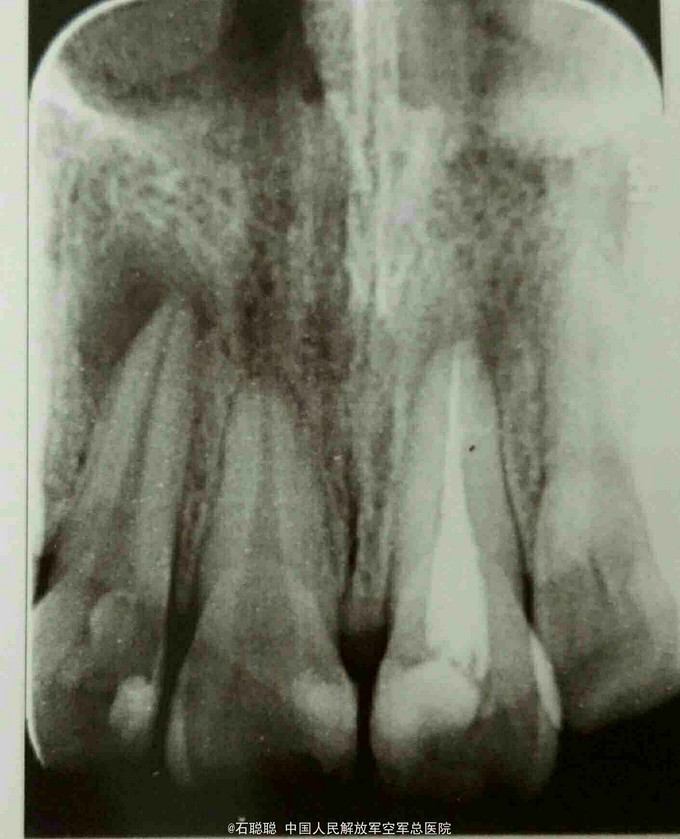

检查:21牙体变色,切缘磨耗不均匀,舍面见牙色充填体完整在位,无松动,叩痛-,牙龈未见明显异常。 根尖片:21根管内高密度充填影像,恰填;12根尖远中见直径约3mm低密度透射影像 曲面断层:36、46残根,根尖低密度影